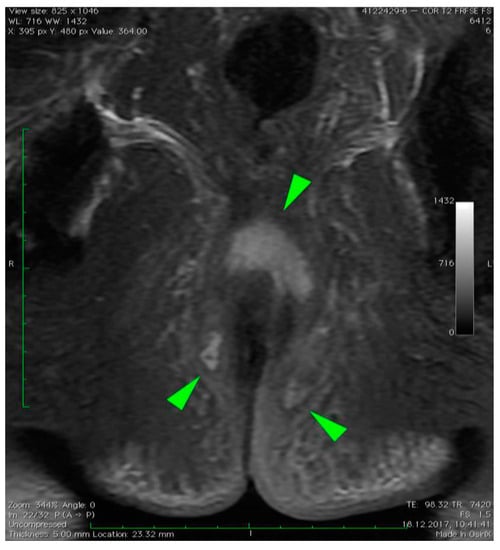

2.2. Radiologic Imaging

3. Case Presentation